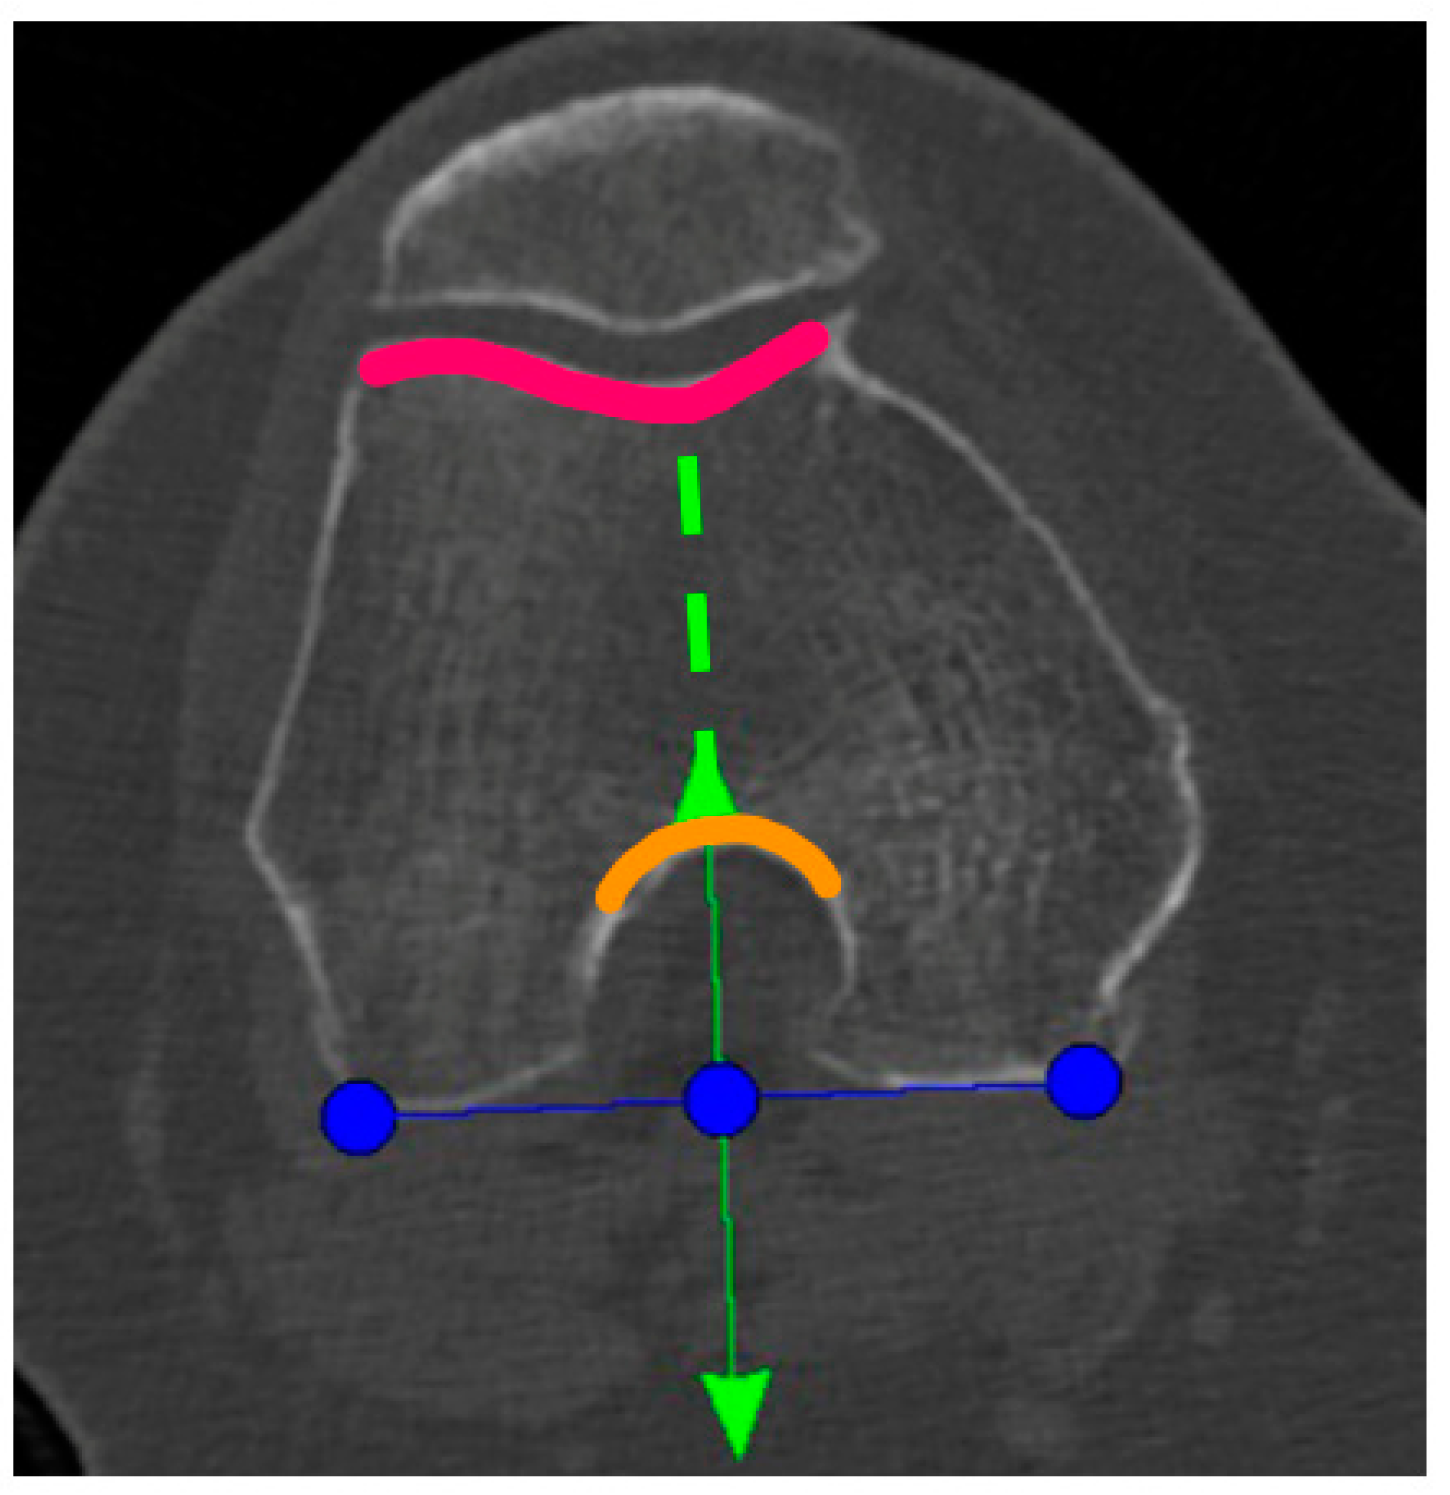

A Preoperative CT-scan of the hip, knee, and ankle was conducted following the standard MAKOplasty protocol and uploaded to STRYKER proprietary platform (Stryker, Mahwah, NJ, USA). Based on this scan, an individual knee model was segmented by the on-site MAKO product specialist (MPS) and used for the primary surgical planning according to the STRYKER standard protocol. Only the tibia-rotation landmark was not set based on tibia landmarks, as suggested, but on the femoral anatomy. In the menu to set the tibia rotation, the scan was scrolled up to the femur and the landmark was then co-aligned to the posterior femur condyles centered in the middle of the notch (Figure 1). Here, the anterior arrow should match the trochlea groove. If there was a relative internal rotation to the trochlea groove, the rotation was adjusted until it met the groove and was captured as the “new” femur-based tibia rotation landmark (Figure 1).

Figure 1.

Blue line: tibial rotation landmark co-aligned to the posterior femoral condylar line. Green line: perpendicular to the blue line and centered to the middle of the notch (anterior green arrow and orange curved line) and the trochlea groove (green dotted line and pink curved line).